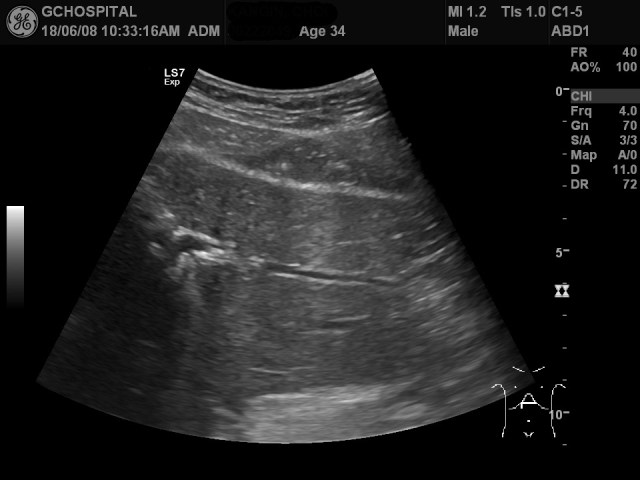

34세 남자 환자로 건강검진 목적으로 내원하여 간초음파를 시행하였으며, 특이소견은 보이지 않았습니다. 위의 두 영상은 간 좌엽을 촬영한 것으로, 환자의 양쪽 흉곽 사이가 좁아서 탐촉자가 잘 들어가지 않아서 횡단면 영상을 얻기가 어려웠습니다.

이 환자는 폐암의 선별검사를 위해 low-dose chest CT도 같이 시행하였는데, 초음파영상에서는 발견하지 못했던 저음영의 단순낭종을 간좌엽 윗부분에서 발견하였습니다.

이번 사례에서처럼 초음파영상 중에는 간좌엽을 별다른 지장 없이 다 확인했다고 믿고 넘어갔으나, 다른 검사에서 미처 발견하지 못했던 병변을 발견하는 경우가 종종 발생합니다. 특히 간 좌엽의 윗부분은 윗쪽 종격동의 fat tissue와 stomach gas shadow와 같이 초음파 빔의 진행을 방해하는 구조물들이 많기 때문에 간 우엽의 지붕부위 못지 않게 주의를 기울여야 하는 부위입니다.